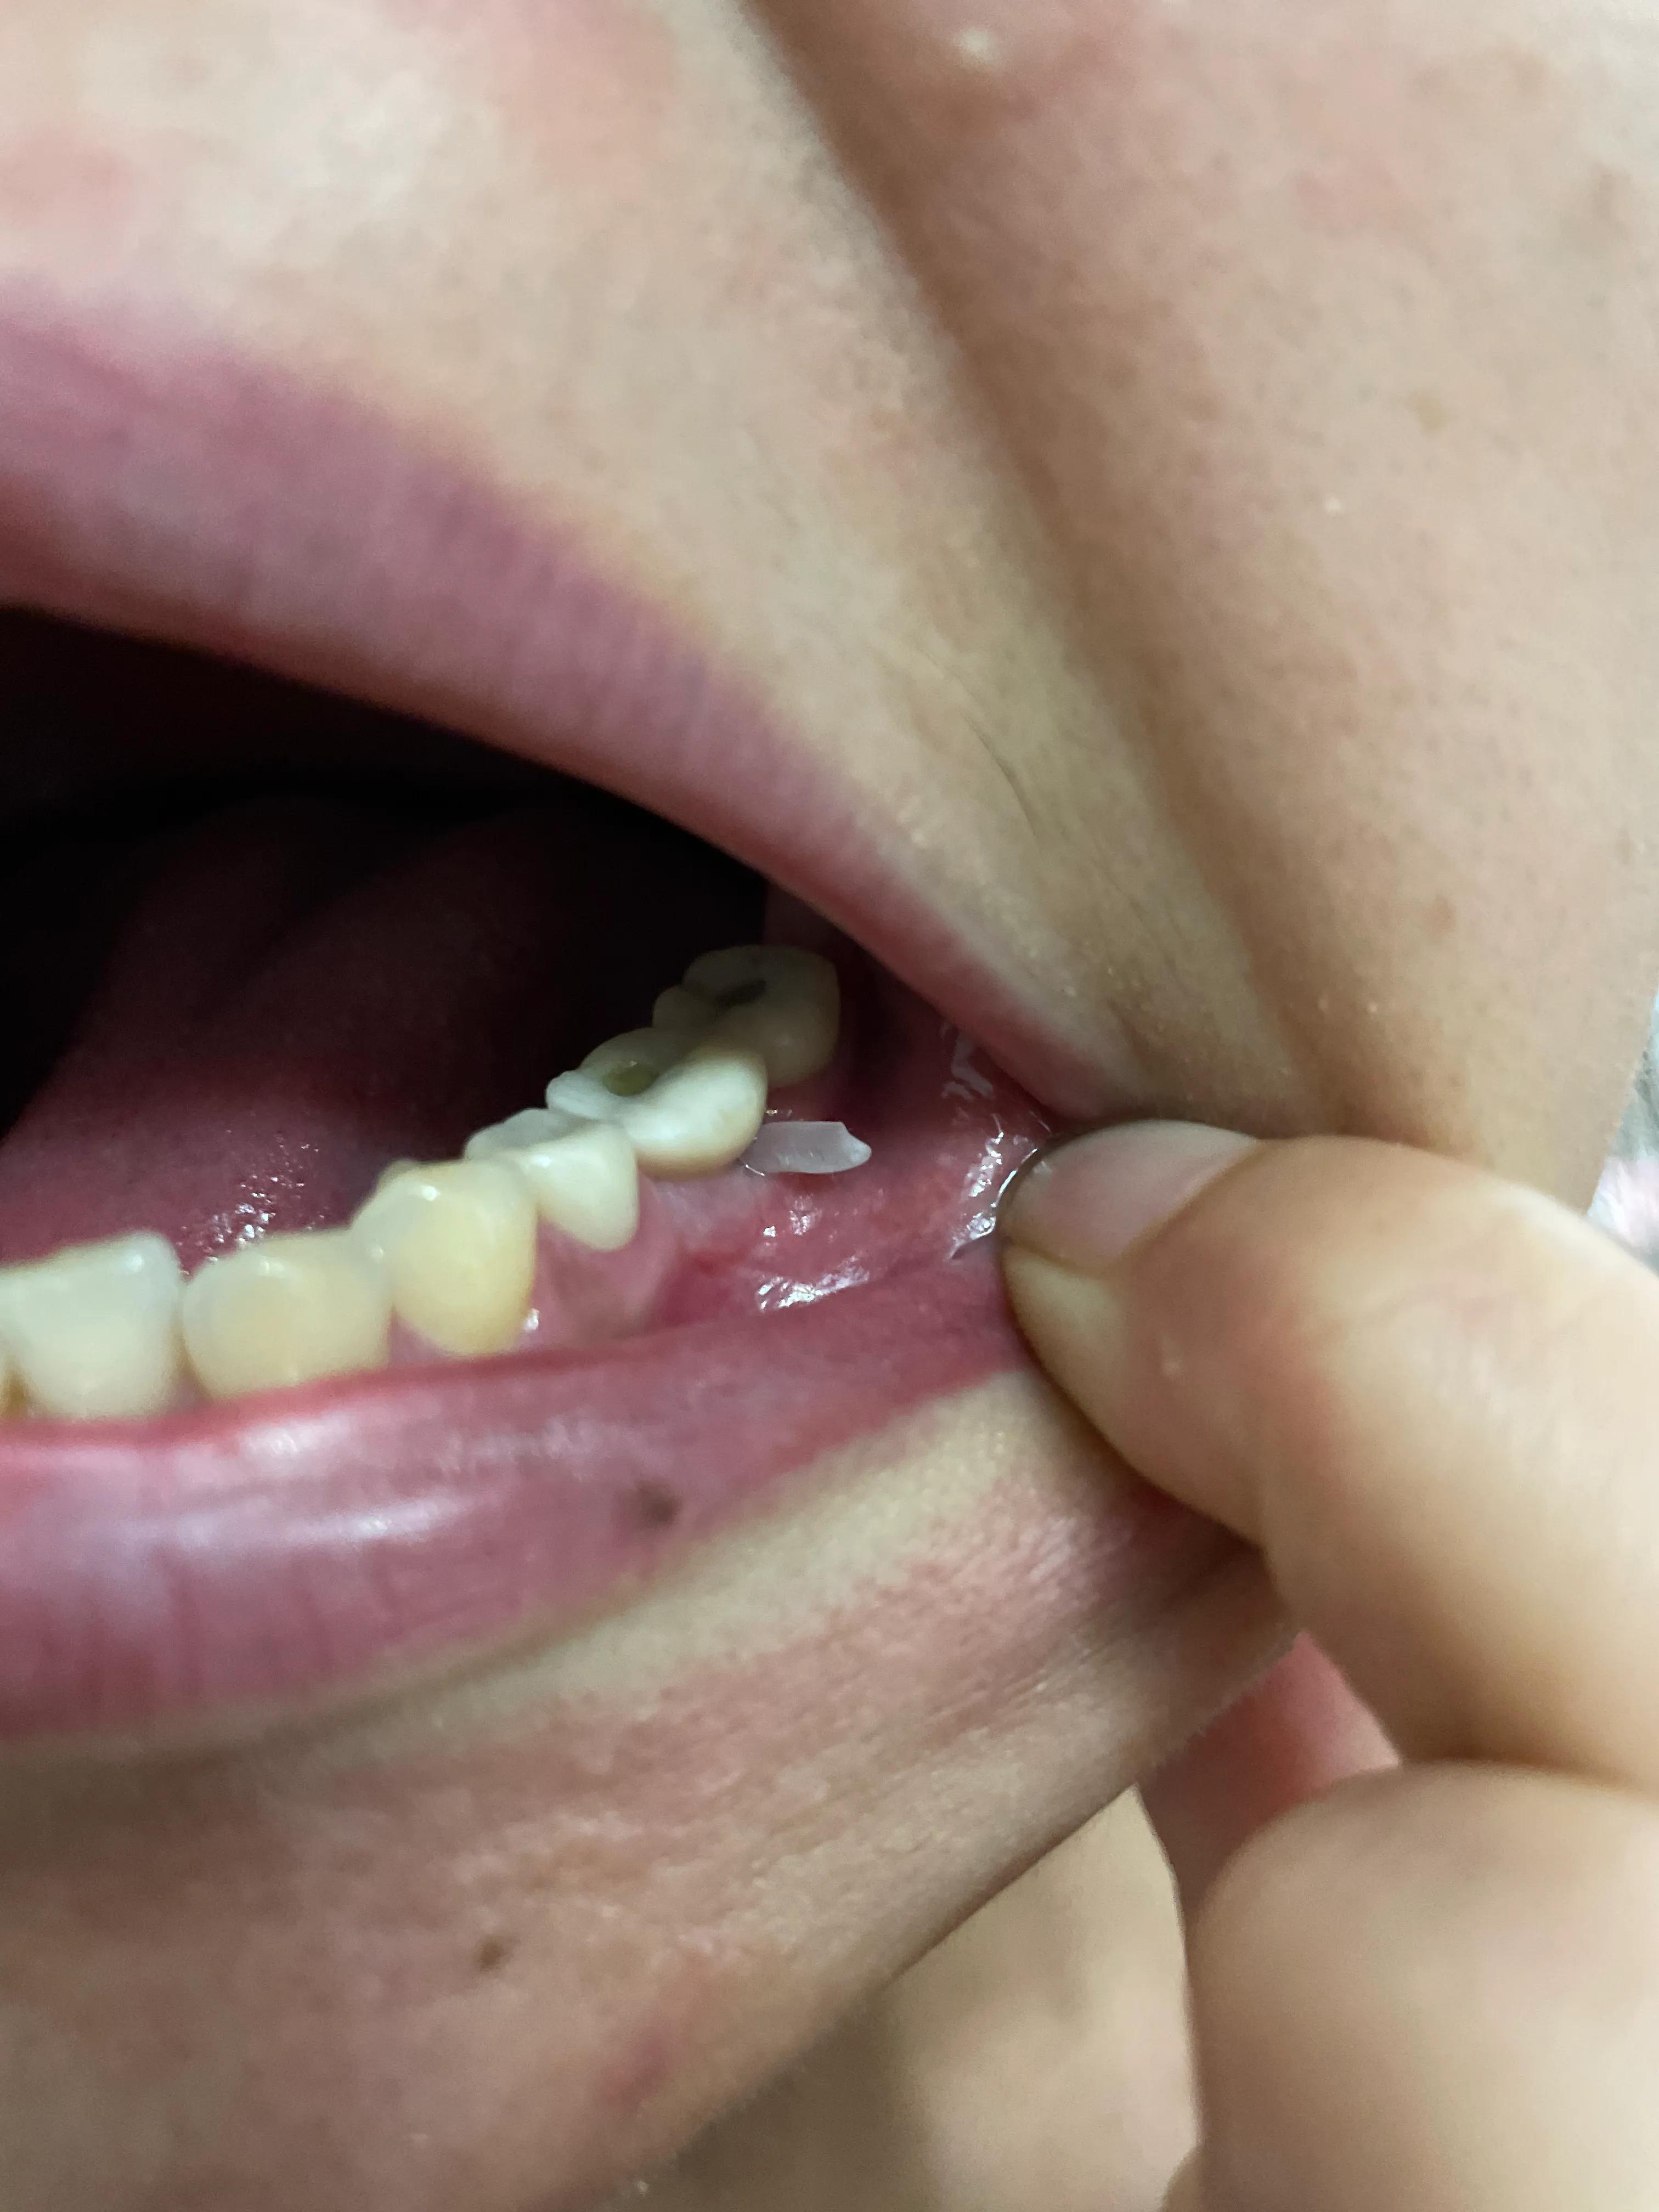

第二副牙帶好 發(fā)現(xiàn)牙齦又缺肉了 更別提貼合牙齒了 而且是一直的疼 一直難受

牙齦是外翻和牙齒分開的 顏色發(fā)白 和其他部位牙齦不是一樣顏色

我不是專業(yè)醫(yī)生 不懂他們所說的正?,F(xiàn)象都包括什么 要怎么后期維護(hù) 我現(xiàn)在先不講看不見的難受 疼 先講直觀能看見的 他們哪位醫(yī)生可以做到把大米粒塞到牙齒下面 和將近半厘米的塑料條塞過他們的牙齒 吃過東西就要用沖牙器 不然隔頓就臭了

沒辦法自己又出去拍片子 找原因 看了幾家醫(yī)院 才知道連種植體也種偏了 牙冠也沒有就位………